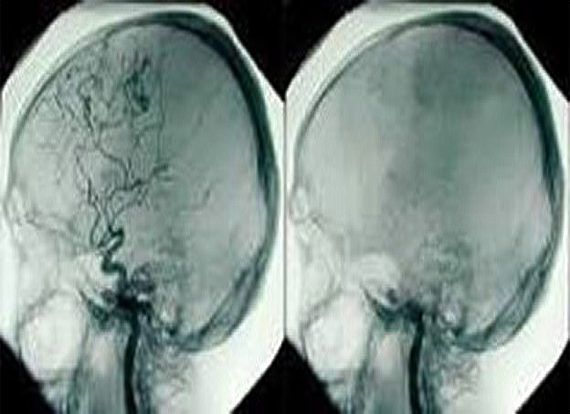

– A stroke

– Cerebral infarction and Cerebral hemorrhage